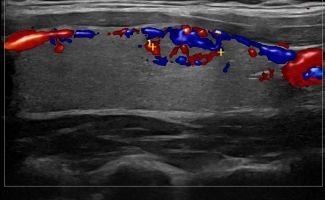

Με την τριπλή μελέτη του Θυρεοειδούς Αδένα, που περιλαμβάνει το B-Μode, το Έγχρωμο Υπερηχογράφημα και την Ελαστογραφία, γίνεται μια ολοκληρωμένη χαρτογράφηση του θυρεοειδούς αδένα. Το περίγραμμα, η αγγείωση και η ελαστικότητα του αδένα, καθώς και η υφή μίας πιθανής βλάβης αξιολογούνται με ακρίβεια και αξιοπιστία.